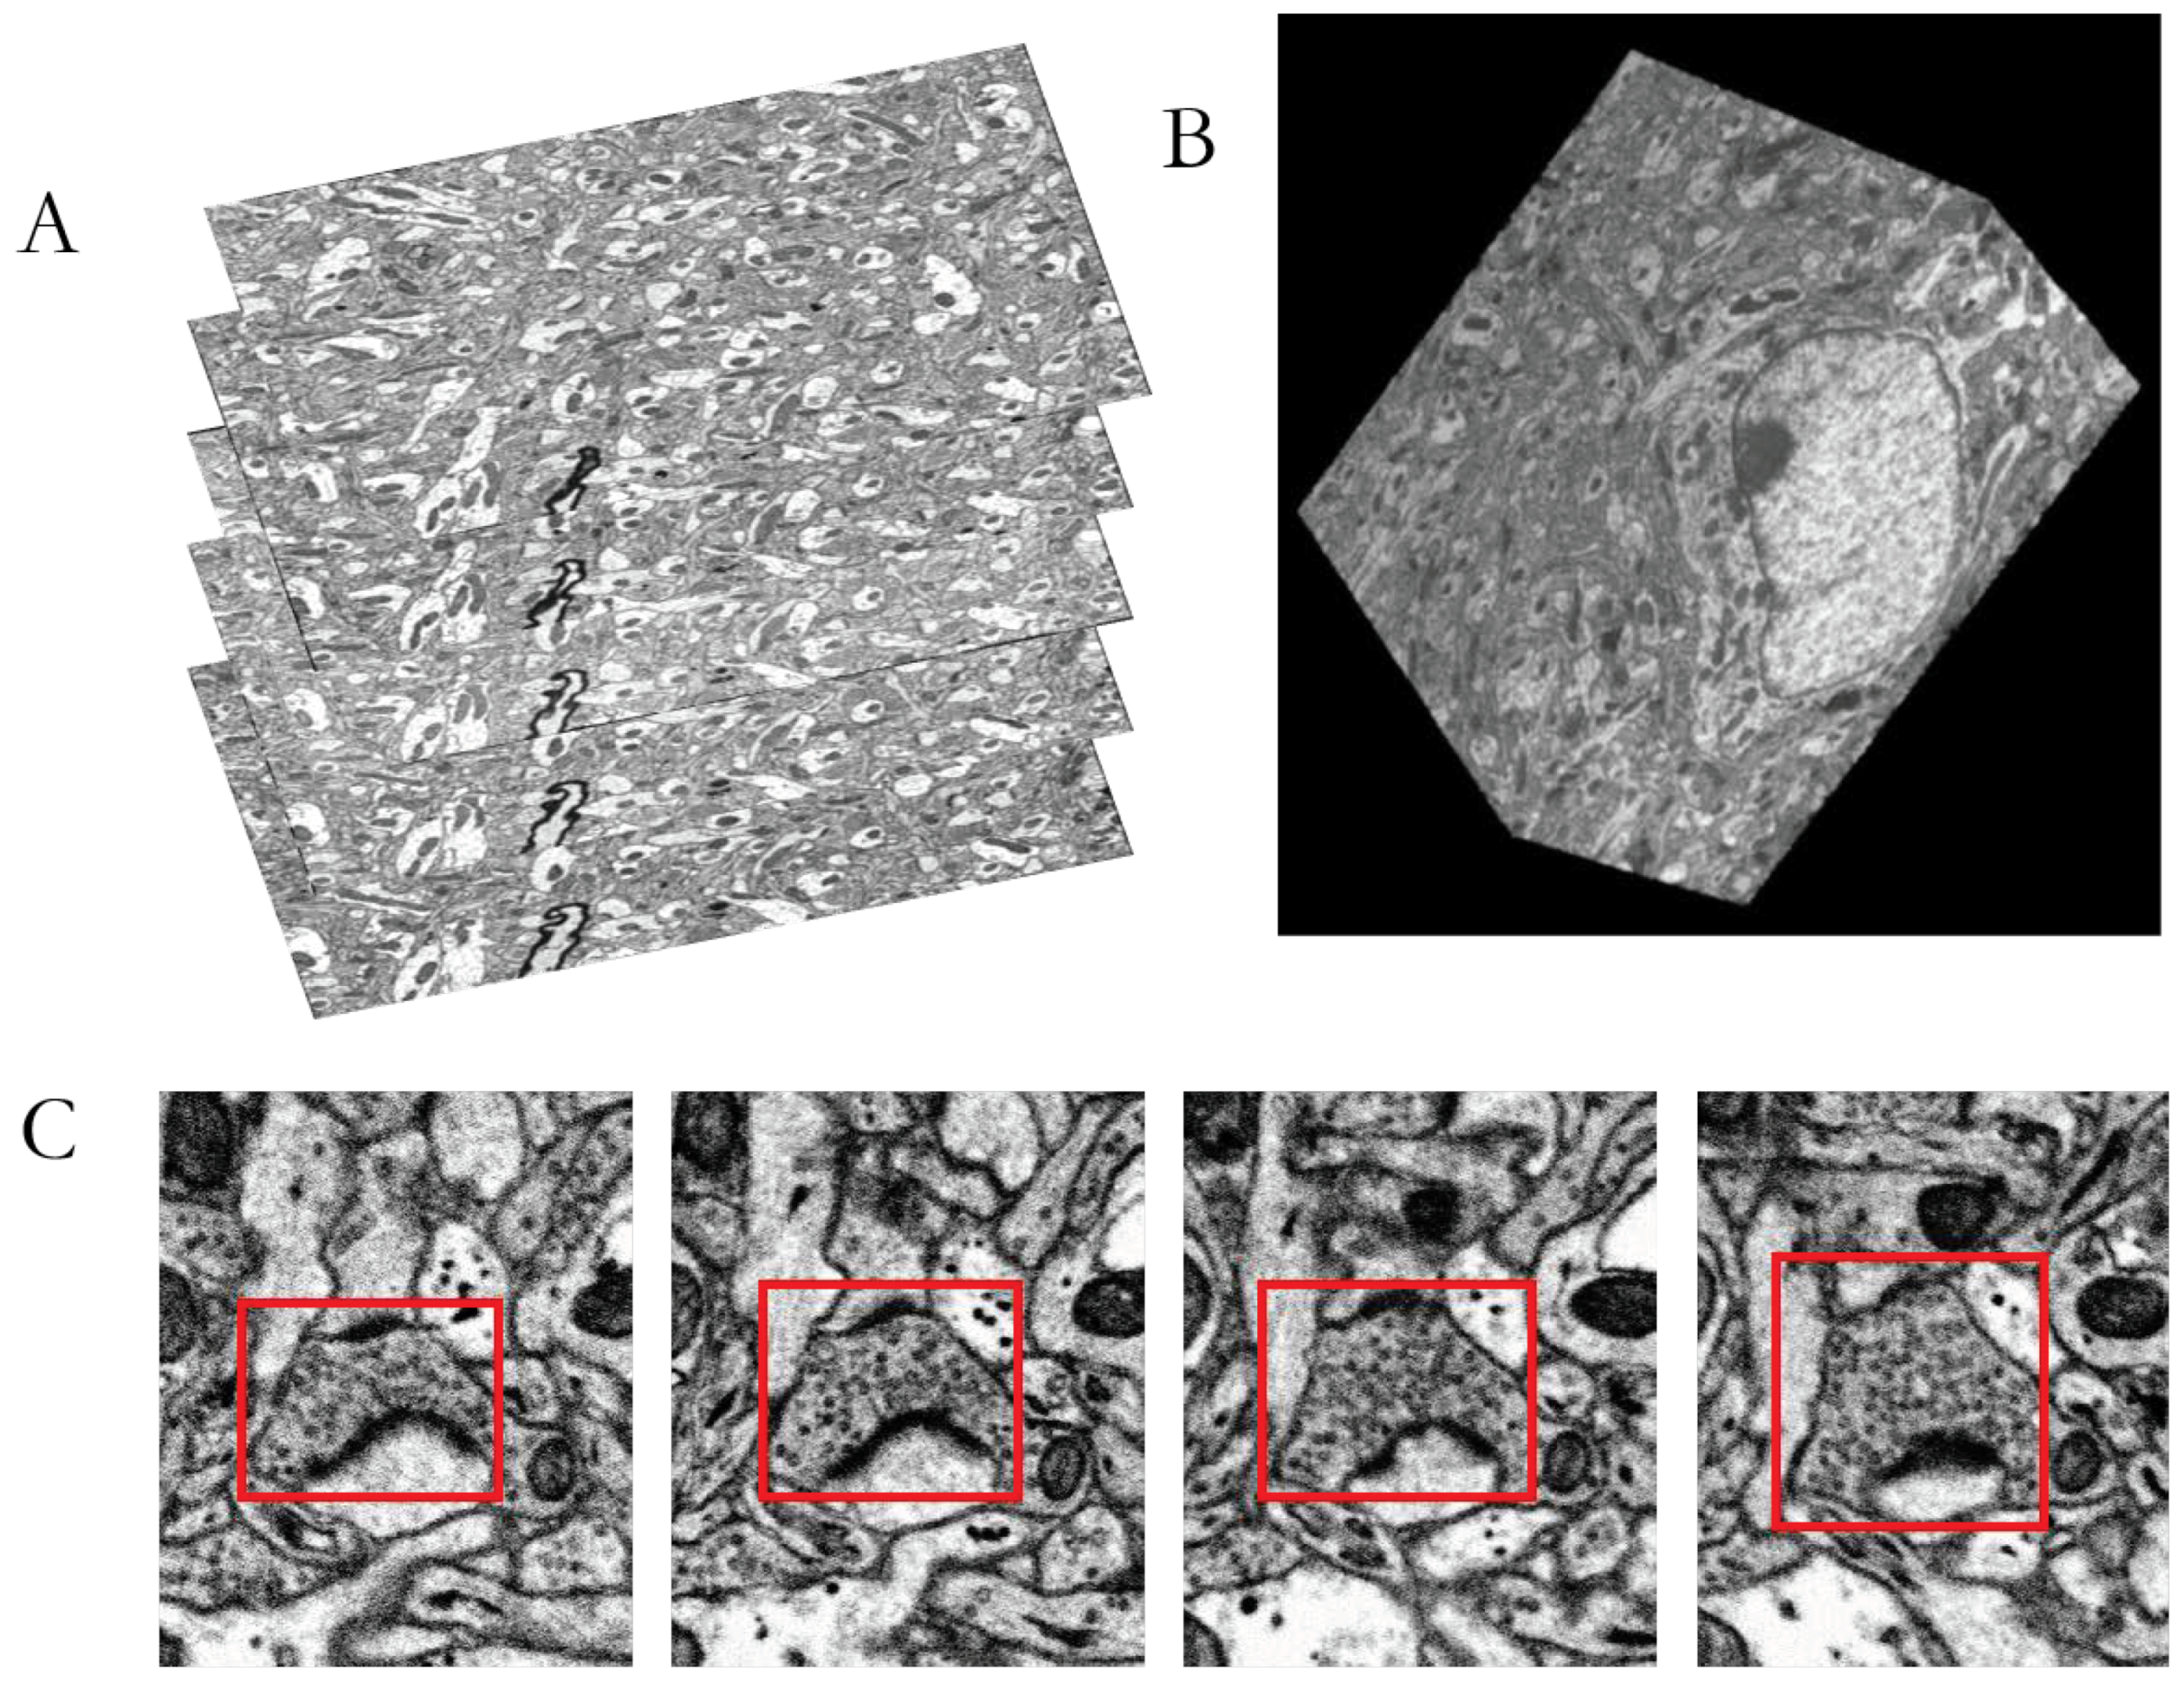

2. Materials

3.1. Image Preprocessing